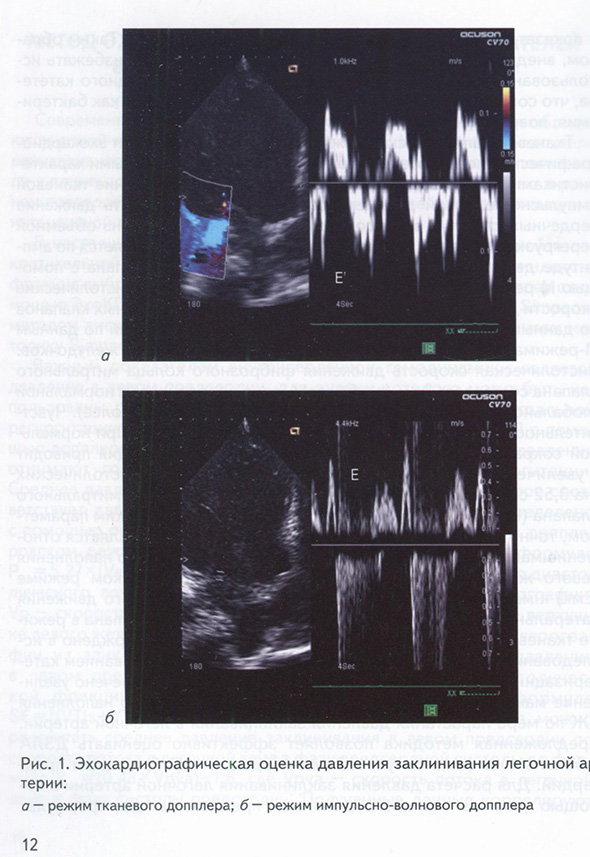

Метод эхокардиографии в оценке показателей внутрисердечной гемодинамики